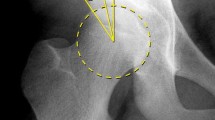

The method described in this paper was used to determine volume and axis orientation in two patients. Computer models of the pelvis were created based on preoperative evaluative CT scans in Case 1, a 13-year-old boy with cerebral palsy and left hip joint dislocation (Figure S1a), and Case 2, a 13-year-old girl with cerebral palsy and right hip joint dislocation (Figure S2a). The results are summarized in Table S1 and depicted Figures S1b and S2b. Comparison of measurements of normal and pathologic acetabula in these patients shows large differences in acetabular orientation in the spastic hip. The acetabular axis determined using our method has a completely reversed orientation under dysplastic conditions (retroversion, posterior tilt, inclination over 90 degrees), which may influence decisions regarding surgical redirection of the acetabulum. These cases demonstrate the applicability of our method in clinical treatment. There are also differences between both dysplastic acetabula with regard to volume, a result that does not support the common view of a shallow, small-volume dysplastic acetabulum. It should be noted, however, that these are only two cases and that further investigation is warranted. Figure S1. Standard X-ray and CT reconstruction in case 1, a 13-year-old boy with cerebral palsy and left hip joint dislocation: (a) Pelvic anteroposterior X-ray; (b) pelvic 3D CT reconstruction showing the position of the acetabular axis. 3D, three-dimensional; CT, computed tomography. Figure S2. Standard X-ray and CT reconstruction in case 2, a 13-year-old girl with cerebral palsy and right hip joint dislocation: (a) Pelvic anteroposterior X-ray; (b) 3D CT reconstruction showing the position of the acetabular axis. 3D, three-dimensional; CT, computed tomography. Table S1. Surface, volume, and spatial orientation of the acetabulum.